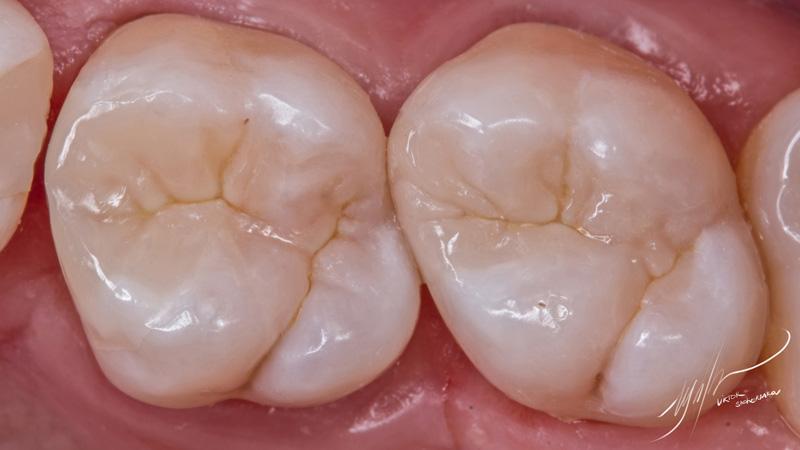

Основной оттенок для восстановления морфологических элементов – Ceram-x SphereTec A3. В качестве материала для финального моделировния был использован Filtek Ultimate White.

Его плотная консистенция дала ощутимые преимущества, потому что особенность данного этапа – работа чрезвычайно маленькими порциями для заполнения пространства между гребнями с формированием тонкой фиссуры.